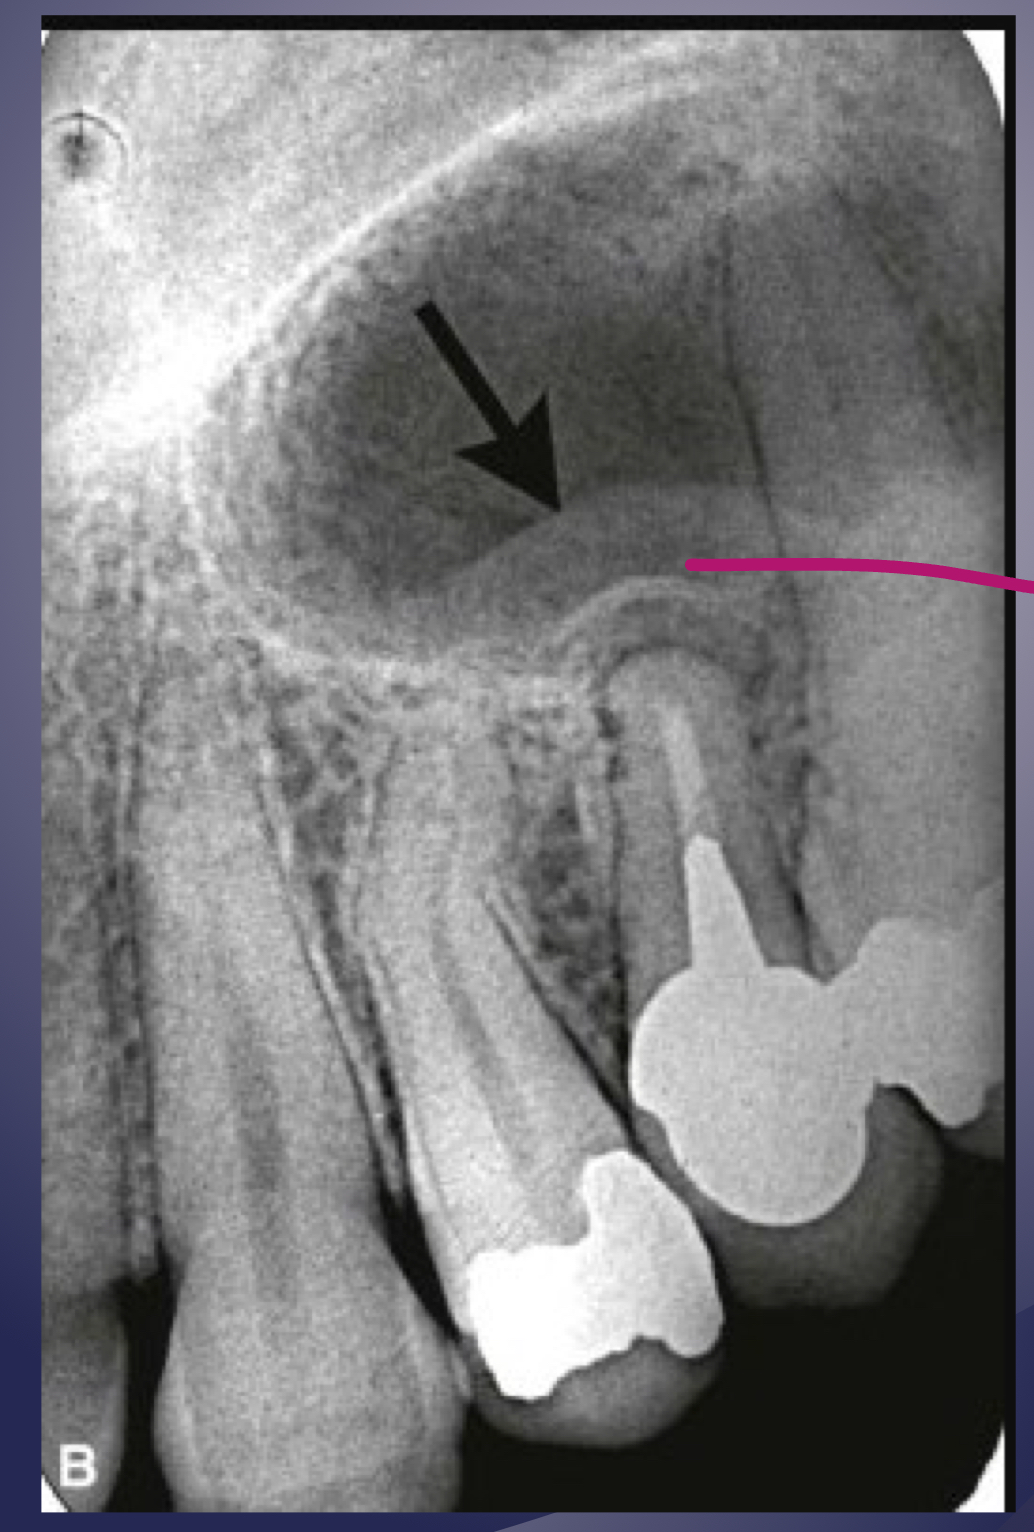

rarefying osteitis

rarefying osteitis (LD gone and radiolucency)

chronic inflam with a non-vital toothÂ

radiolucent due to removal of bone

sequelae of acute episodeÂ

includes abscess, granuloma, or radicular cyst (these three have no distinction radiologically)

bone deposition around area of rarefaction

sclerosing osteitis + radiolucency